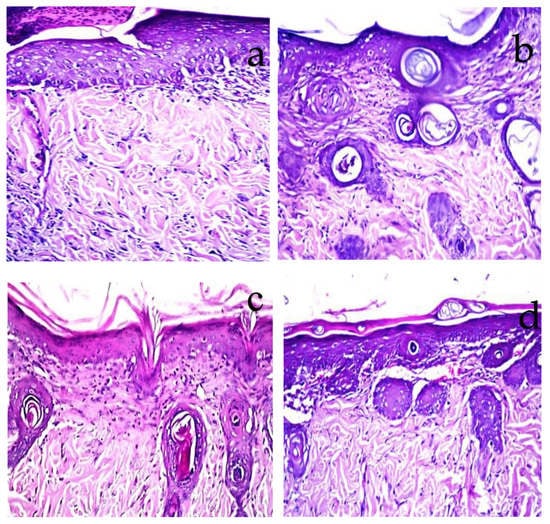

2.7. Histopathological Observations